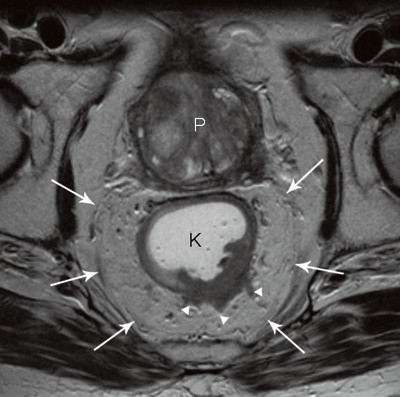

MR

MR-undersøkelse med overflatespole er i dag standard ved rectumcancer i Norge. Metoden gir en god anatomisk oversikt over hele bekkenregionen og innebærer høy grad av nøyaktighet i kartleggingen av lokal tumorutbredelse. Evalueringen av T-stadium med MR har vist svært varierende resultater, fra 65 % til 86 % (19) – (23). Overestimering av T2-tumorer og underestimering av T3-tumorer er de vanligste feilene. I likhet med endorektal ultralyd kan heller ikke MR skille en desmoplastisk reaksjon rundt tarmen fra lettgradig malign innvekst. Den mesorektale fascie, som i de aller fleste tilfeller representerer den kirurgiske reseksjonsrand, identifiseres imidlertid lett, og avstanden mellom tumor og fascie kan måles med høy grad av nøyaktighet (fig 4). Det er vist at denne avstanden er en viktigere prognostisk faktor enn T-stadium i seg selv.

Evalueringen av status for kirurgisk reseksjonsrand blir svært nøyaktig med MR (4, 19, 21, 24 – 27). Reproduserbarheten ble nylig også evaluert i en stor multisenterstudie. 679 pasienter ved 11 europeiske sentre ble undersøkt, og 311 av disse ble primæroperert. Resultatene viste 92 % nøyaktighet i evalueringen av om kirurgisk reseksjonsrand var involvert eller truet (tumor innen 1 mm fra fascien) (28) (fig 5). Man undersøkte i denne studien også hvor nøyaktig MR kunne fastslå tumors dybdeinfiltrasjon i mesorectum utenfor muscularis propria (29). Den gjennomsnittlige forskjellen mellom infiltrasjonsdybden målt med MR og dybden målt ved histopatologisk analyse var – 0,05 mm.